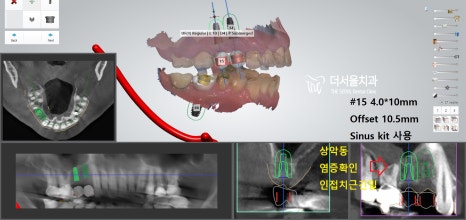

『# 14 # 15 # 46 implant

디지털 방식의 분석을 이용하여

식립 방향 및 각도를 결정하고

최종적으로 심어질 위치까지 선정했습니다.

이후 계산된 곳에 튼튼한 픽스처를 심어드렸죠.

# 47은 심어져있던 픽스쳐 위에

크라운을 올려드려야 되는 과정이라

어려움이 있었는데요.

# 47 기존 크라운 제거

방사선 엑스레이 촬영으로

제품명과 사이즈를 판독한 뒤

관련 부품을 수급하여

# 46 크라운을 올릴 때 같이 해드렸습니다.